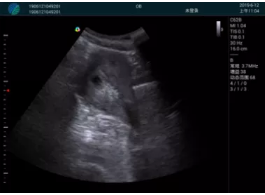

可視化甲狀腺穿刺引導(dǎo)

頸動(dòng)脈血流充盈飽滿,無外溢

肝內(nèi)血管顯示清晰,血流敏感無外溢

病例二:

甲狀腺囊性結(jié)節(jié),囊壁鈣化,透聲好

甲狀腺囊性占位